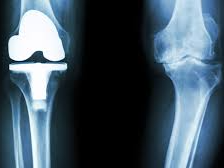

나이가 들면 관절 사이 연골이 점차 닳아 없어지면서 뼈와 뼈가 직접 맞닿아 통증을 유발합니다. 특히 무릎은 체중을 지탱하는 관절로써 손상되기 쉬우며, 다음과 같은 증상이 있다면 인공관절 수술이 필요할 수 있습니다.

이런 경우에는 무릎 인공관절 치환술이 가장 효과적인 치료법으로 여겨지며, 수술 후에는 통증 완화 및 활동 능력 회복이 가능합니다.

일반적으로 무릎 인공관절 치환술은 한쪽 무릎 기준 300만 원에서 500만 원까지 발생할 수 있습니다. 수술 전 검사비, 입원비, 인공관절 재료비, 수술 후 재활치료까지 포함하면 금액은 더 늘어날 수 있습니다.